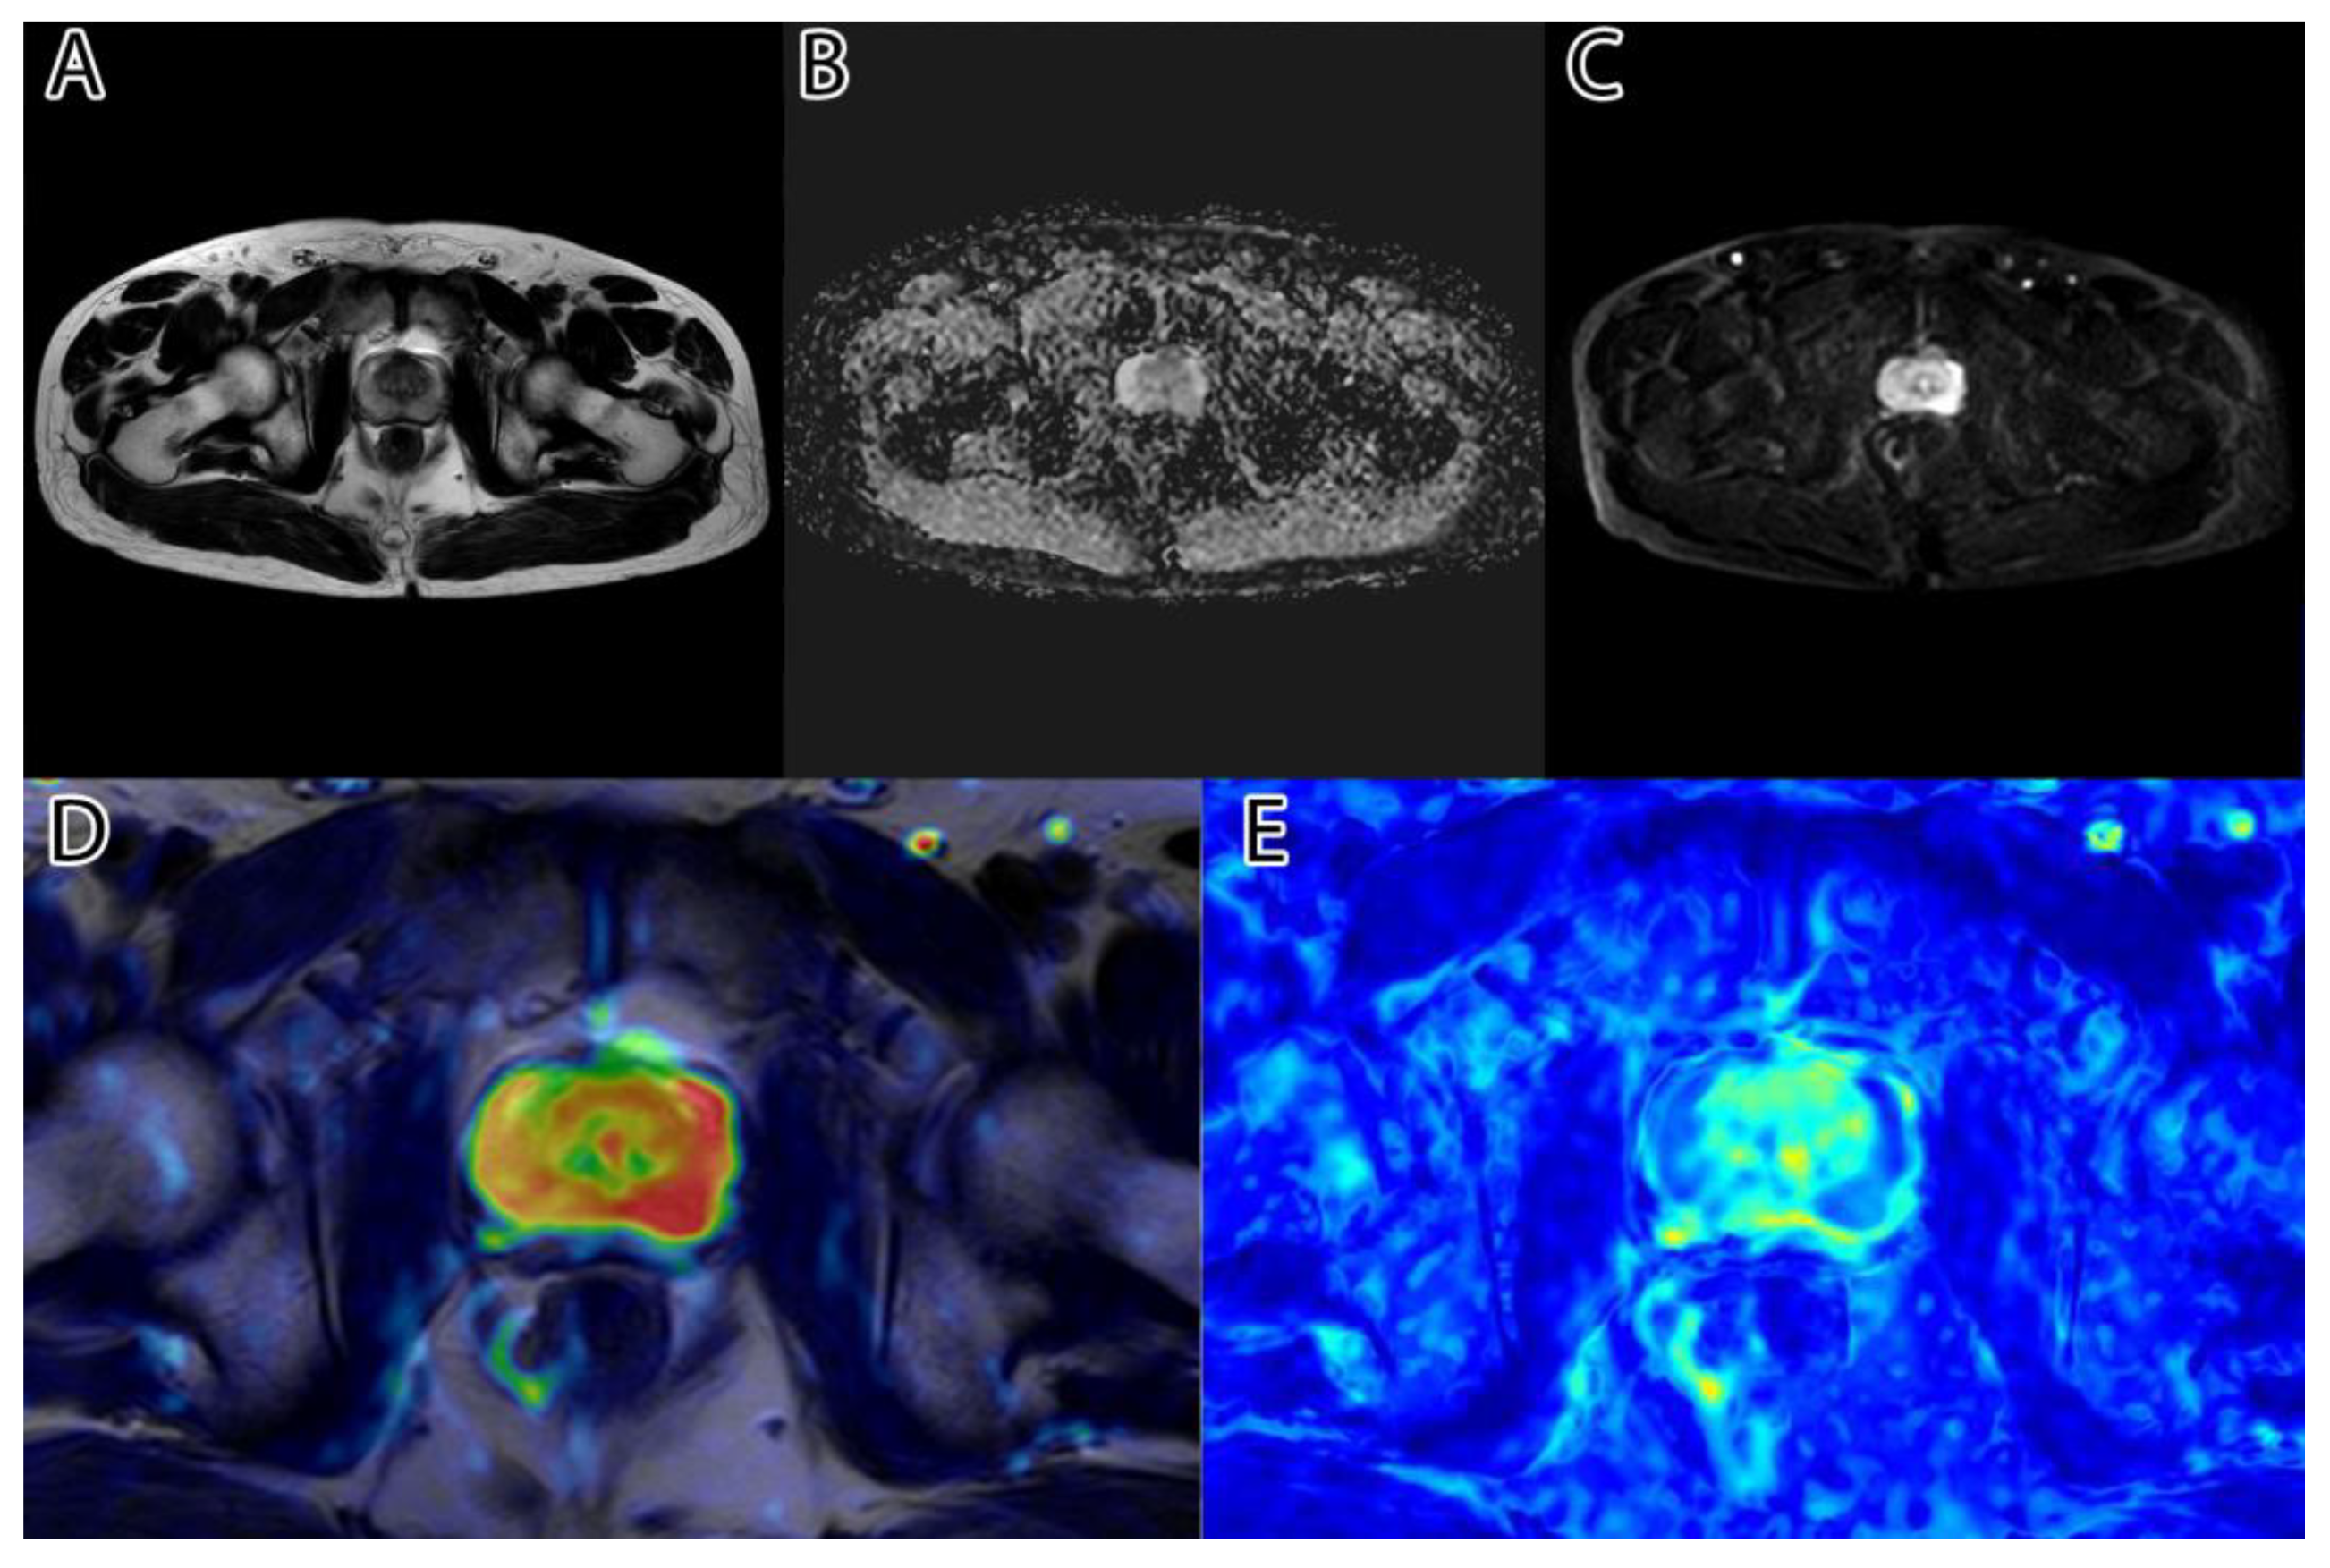

The second step was to compute the inversion of T2WI and ADC, thus obtaining the area of interest (tumor) represented by higher intensity values, as seen in Figure 1D,E. For this, we subtracted the actual image values from the maximum of 255.

Figure 1. Sample image: (A)—T2WI; (B)—ADC; (C)—DWI; (D)—inverted T2WI; (E)—inverted DWI; (F)—RGB images resulting from image fusion of (CE).

The third step was to combine the three images into an RGB (red, green, blue) image. T2WI was used for the red channel, ADC was used for the green, and DWI was used for the blue. The resulting image can be seen in Figure 1F.

The sixth and final step was to compute the final intensity mask by subtracting the square root from the square sum of the alpha–beta channels and subtracting the resulting value from the luminance. The resulting intensity image can be seen in Figure 2B and Figure 3B. By adding the ‘jet’ color map to it, we obtained a colored intensity map that highlights the tumoral areas, as seen in Figure 2C and Figure 3C.

The algorithm was used on all 204 images and computed the tumor intensity image. A sample from the original data, and the resulting fused image, can be seen in Figure 1.